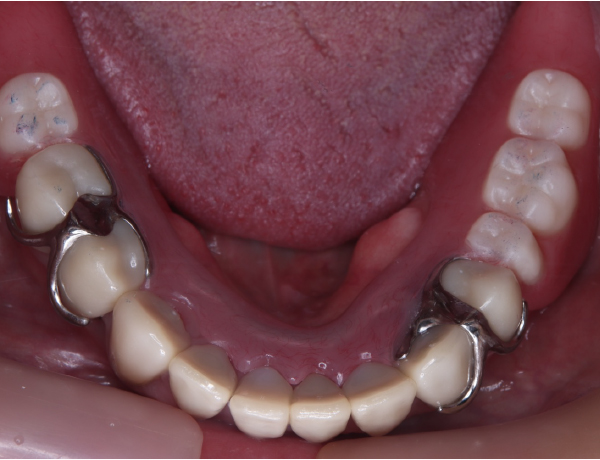

下あご

赤丸の部分は、骨隆起になります。下あごにも骨の隆起があります。

下あごには、入れ歯が入っていません。天然の歯が残っていますが、奥歯は何本か抜けてしまっている状態です。

こうしたアンバランスにより、上あごの入れ歯に負担がかかり歯が抜けている可能性も高いと判断しました。天然の歯にかぶせ物を行い、保険で下あごの入れ歯を作製しました。

下の入れ歯も良く折れたり壊れたりしてしまうとのことでしたので、細い部分や力のかかる部分は、金属にしました。金属にした場合に、骨隆起が多い患者さんは、入れ歯めり込んだりして、痛みの原因になりかねないので、注意が必要です。

下骨隆起の部分を上手く避けて作製されているのが分かると思います。普通の金属の入れ歯ですと覆うのですが、それだと分厚くなり過ぎてしまうので、上手く骨隆起を避けて作製しています。

左右のかみ合わせも非常にバランス良く噛ませています。また、バネの部分を上の歯が噛み込まないように工夫をしています。良くこのバネの部分で折れてしまう場合がありますので、それを考慮してあります。